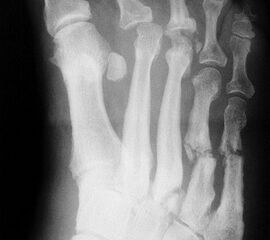

Abbildung 4

DNOAP Typ III (Abb. 4)

Betroffen sind hier das Chopart-Gelenk, also das Talonaviculargelenk und das Calcaneocuboidgekenk. Ein Beteiligung des Naviculocuneiformgelenks ist möglich. Das Längsgewölbe bricht zusammen und es entsteht der klassische diabetische Schaukelfuß – die Kombination aus einer reduzierten Inklination des Kalkaneus in Verbindung mit einer distalen Hackenfußstellung. Nach plantar prominente Knochenkanten und -fragmente können hier ebenfalls zu Ulzerationen der Fußsohle führen.